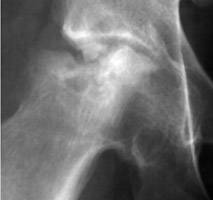

One image each of two separate patients with collapse and necrosis of the femoral head, both of which are secondary to repeated injection of steroids. A rapid progression of change in a joint secondary to steroid injections. Transition of a joint from one of minor alterations(such as narrowing, sclerosis) to one of significant bony fragmentation and collapse. Gouged-out areas of bony destruction may be similar to small animal bites, hence the bite sign.

AP hip - Click on the image for a larger versionA - Click on the image for a larger versionB